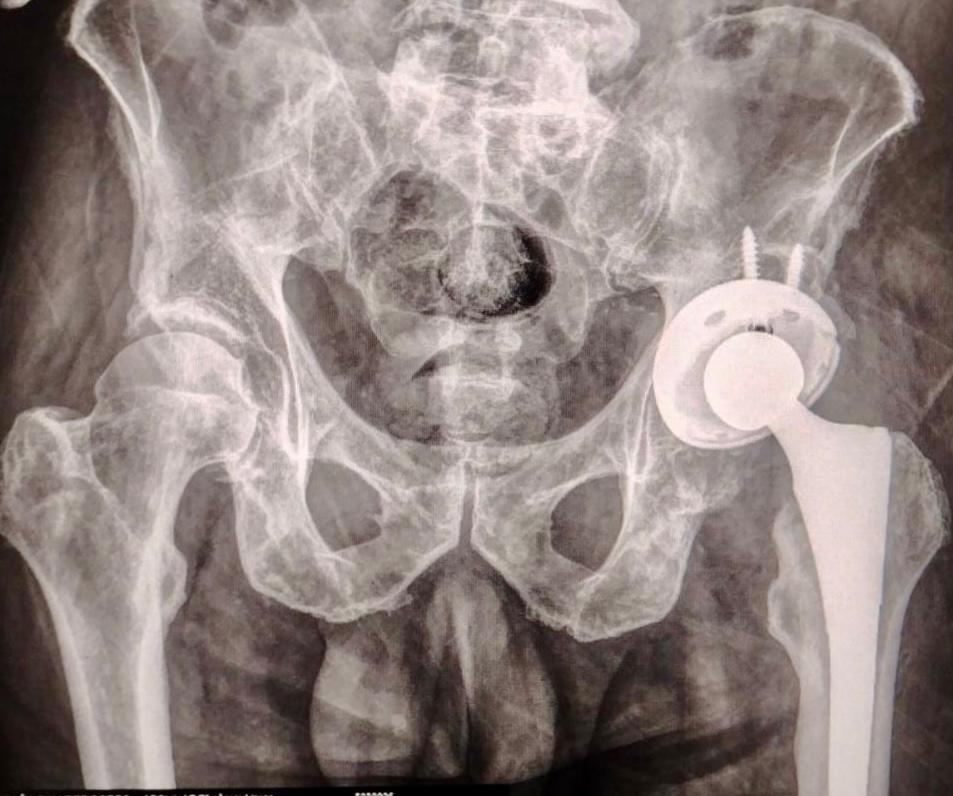

CIUDAD DE PUEBLA, Pue.- El Gobierno del Estado de Puebla a través del Instituto de Seguridad y Servicios Sociales de los Trabajadores al Servicio de los Poderes del Estado de Puebla (ISSSTEP), realizó con éxito y bienestar la colocación de la primera prótesis de cadera sin costo para el paciente, un nuevo hito en el fortalecimiento de sus servicios médicos de alta especialidad.

Al poner en marcha su Programa de Cirugía Articular, el Hospital de Especialidades, no solo está a la vanguardia en la innovación tecnológica para la atención integral de enfermedades osteoarticulares, sino se suma a la política de la bioética social que emprende el gobernador Alejandro Armenta, de garantizar la seguridad en materia de salud de manera profesional y gratuita.

La intervención quirúrgica fue realizada por un equipo multidisciplinario altamente capacitado, bajo estrictos protocolos de seguridad y criterios clínicos de selección. Este procedimiento representa un paso significativo en la atención integral de padecimientos osteoarticulares, particularmente en pacientes con desgaste articular severo que afecta su calidad de vida y movilidad.

Este nuevo programa busca ofrecer alternativas de tratamiento quirúrgico de alto nivel, donde prioriza la seguridad del paciente desde la etapa preoperatoria, durante la cirugía y en el seguimiento posoperatorio. La implementación de tecnologías médicas avanzadas y el fortalecimiento de las capacidades humanas del personal quirúrgico son parte fundamental de esta estrategia.

Asimismo, este logro es resultado del compromiso institucional con la salud de las y los trabajadores al servicio del estado, así como de la visión de consolidar un modelo médico preventivo, seguro y humanizado. Abre la puerta para ampliar gradualmente el acceso a cirugías de reemplazo articular, dado que permite a más pacientes recuperar su funcionalidad y retomar una vida activa con menor dolor y mayor bienestar.